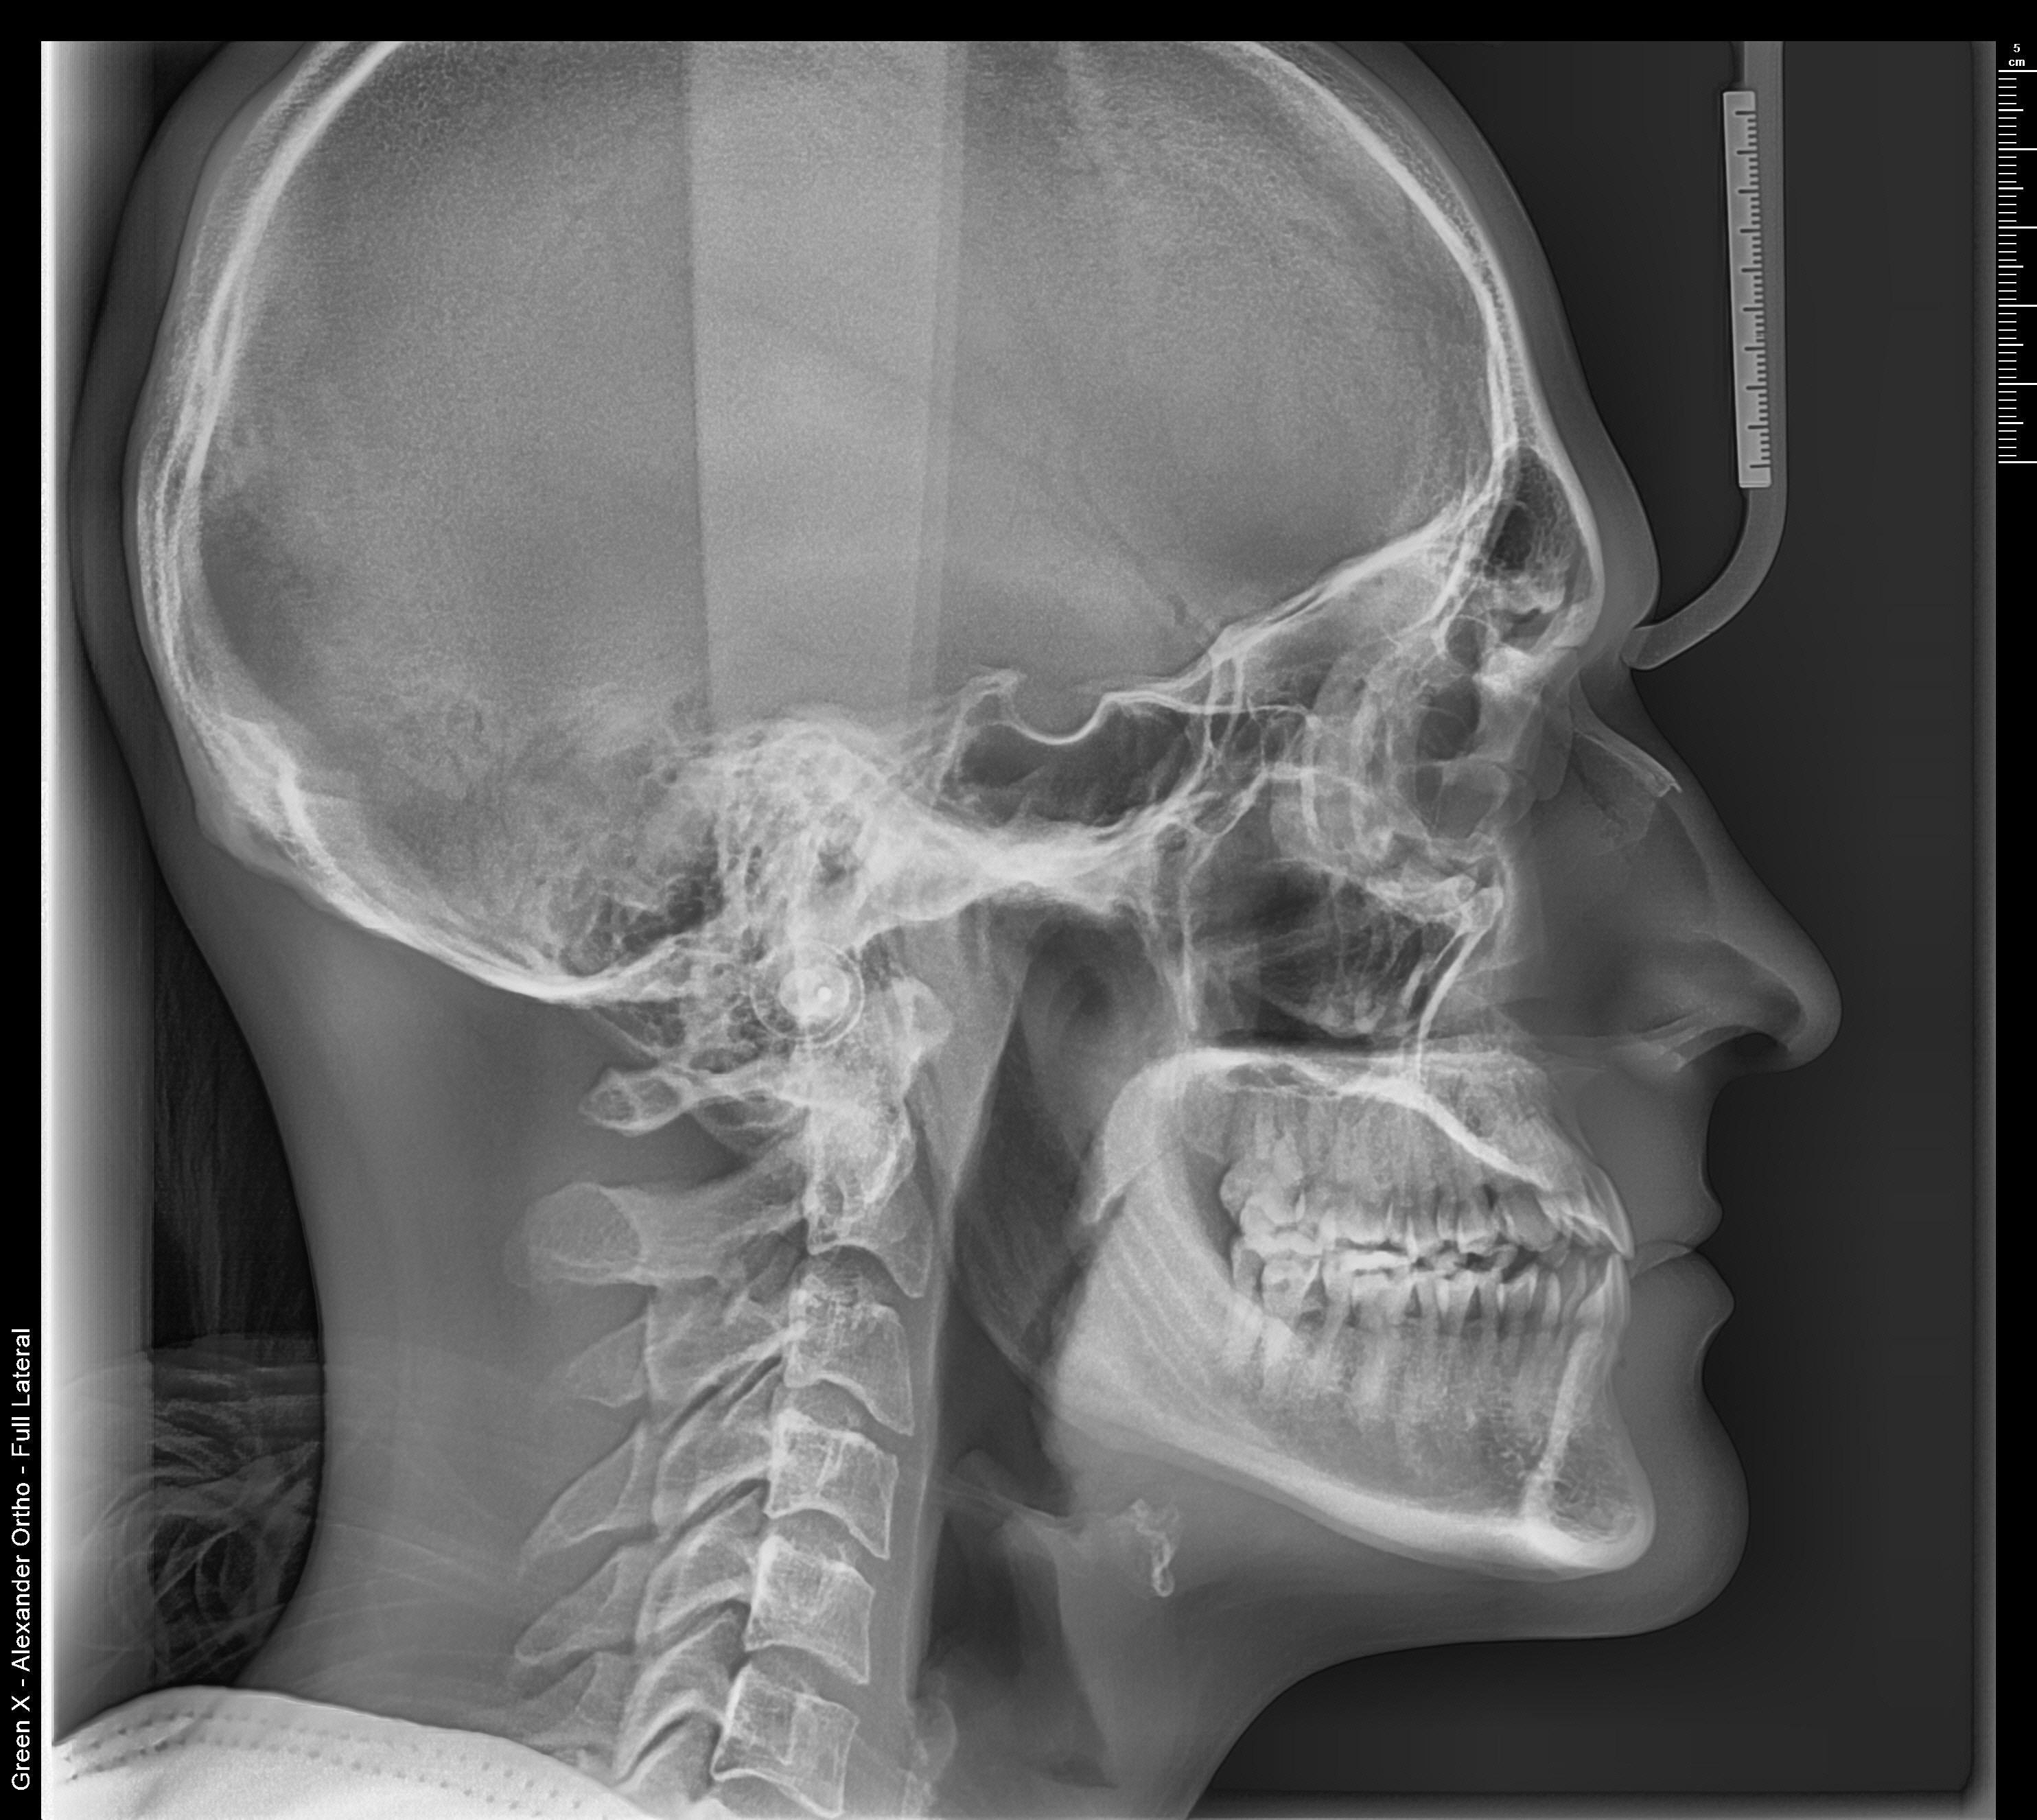

I have a. appointment coming up with my ortho soon and I’m gonna ask about possible surgery because my maxilla is definitely recessed and i have an edge to edge bite.

I was thinking I’d need a 3 piece lefort 1 (to advance my maxilla and widen my palate), BSSO to line up my bite, and a smal CCW rotation of both jaws. I’m curious as to what you guys have to say though and what movements (and amount of advancement) you think I’d need.

Definitely not counterclockwise rotation. Probably just correct the proclination of your upper teeth and get lefort 1 advancement (possibly a little bit of downward movement) . also your chin seems to be prognathic by itself, could use a chin setback.

Yeah get lefort 1 it looks like u got a slight underbite